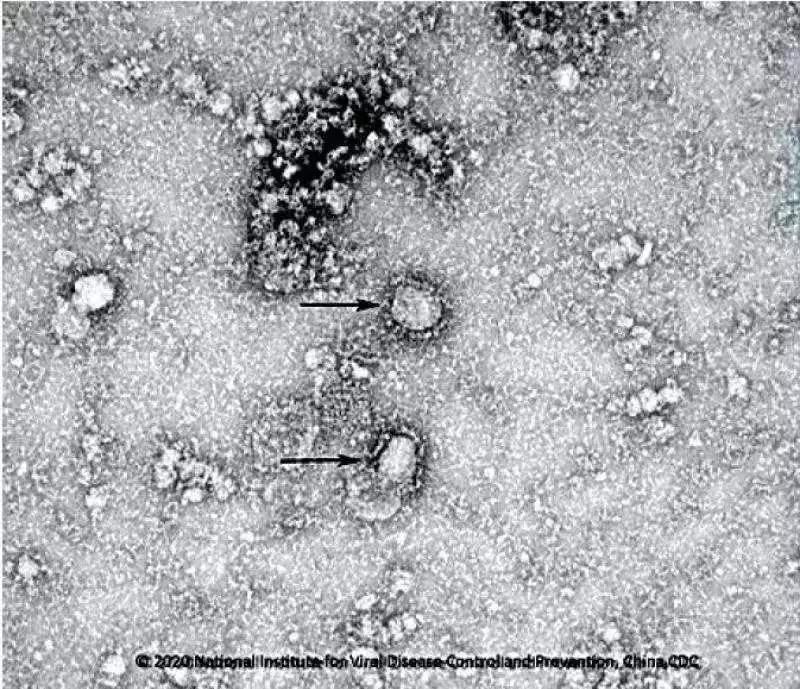

中國疾控中心開始研發(fā)新冠病毒疫苗,已成功分離病毒,正篩選種子毒株。

中國疾控中心已成功分離我國首株新型冠狀病毒毒種